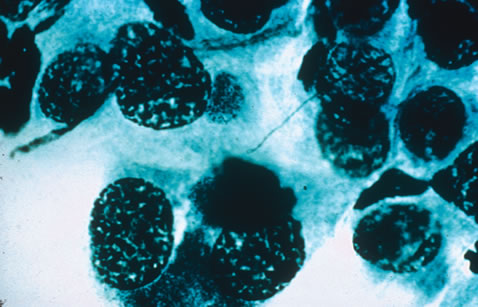

Any cell type may be infected, appearing larger than normal (cytomegalic) and demonstrating eosinophilic intranuclear “owl's eye” and smaller intracytoplasmic viral inclusion bodies, which are better seen with Giemsa or Papanicolaou's stains (Fig. 8). Histologic examination of tissue specimens, including bronchoalveolar lavage fluid and urine, may be useful for diagnosis.

Fig. 8. Typical lesion of cytomegalovirus (CMV) produces retinal necrosis with large cells possessing owl's eye inclusions.